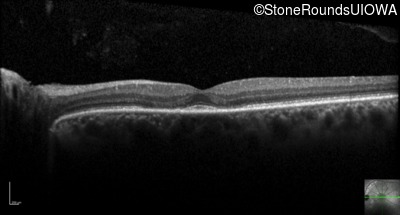

Optical Coherence Tomography - Right - 20/40 -2 sc

Exemplar / OCT Stack